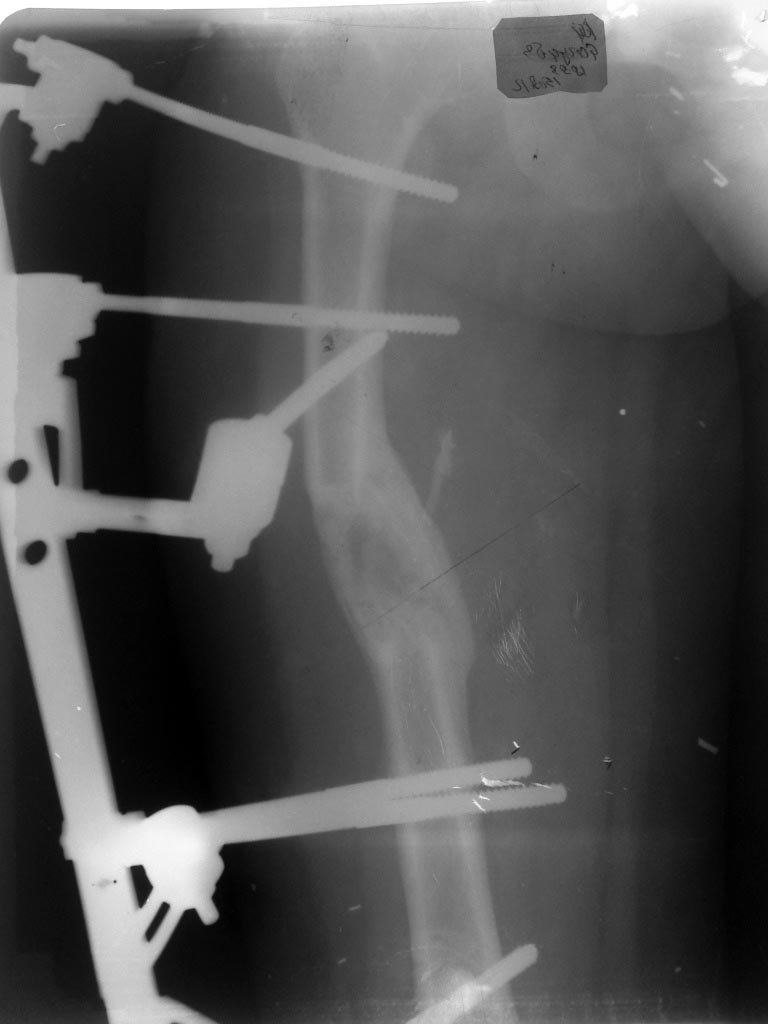

Здравствуйте, уважаемые коллеги!Девочка 13.5 лет, в марте месяце наложили стержневой аппарат МКЦ (произ-во ЦИТО) на бедро в связи с укорочением бедра на 4.5 см, дистракция до мая месяца на 5.5 см, при наложении аппарата на проксимальную часть бедра, неправильно были подобраны стержни- короткие, в связи с чем аппарат перетенул (латерилизовал ) проксимальный отломок, в мае месяце МКЦ констукция для облегчения была заменена на пластину аппарата Илизарова, попытка медиализировать отломок мало помогла. сейчас стоит вопрос об удалении стержней. Можно ли при таком смещении это делать ведь фактически смещение по ширине а не под углом, ? при полной нагрузке не сформируется ли угловая деформация бедра, хотя консолидация хорошая, клинически, ось бедра правильная и симметрична другой ноге.

В настоящее время сформировалась первичная костная ткань. Конечно, коррекцию деформации нужно было проводить на "мягком" регенерате и, конечно, сделать это на монолатеральном аппарате данной конструкции не просто (известный минус монолатералов). Мне кажется нужно демонтировать АВФ и понаблюдать до окончания роста (16-18 лет). Тогда и решить вопрос об окончательной коррекции деформации.

А какие другие варианты возможны? При такой степени зрелости регене6рата исправить уже ничего не получится. Снимайте аппарат, реабилитация - и через несколько месяцев окончательная оценка результатов лечения. Никаких проблем возникнуть не должно.

Применительно к нарушению механической оси это взаимозаменяемые виды смещения.

Вториная деформация формируется в тех случаях, когда аппарат снимется преждевременно, или задается чрезмерная нагрузка, неадекватная прочности регенерата.

Подобное смещение - закономерно и практически неустранимо при использовании монолатеральных конструкций. Устьранить деформацию можно было, применив кольцевую конструкцию с дистрацкцией по внутренней поверхности. Хотя в данном случае эта деформация вряд ли будет иметь клиническое значение.

Apparat konechno strashnovat , regenerat krivovat, no ne strashno.

Strashno kak votknuty half pins medialno- tam

Ved femoral artery !!!

Всем большое спасибо за быстрый отклик по моей проблеме, я думаю на ВСЯКИЙ СЛУЧАЙ еще поддержать 2-3 недели аппарат, потом его демонтировать (состояние кожных покровов позволяет), и уж потом как надо дообследовать и дальше наблюдать как многие советовали. может все и обойдется, только теперь более тщательно буду планировать компоновку аппарата. а по поводу "Apparat konechno strashnovat"

по поводу "Strashno kak votknuty half pins medialno- tam

Ved femoral artery !!!" все стержни в безопасной зоне бедра,

самаое главное ВЫ сказали "regenerat krivovat, no ne strashno" я ведь переживал больше всего из за этого

Ya ughe VTOm vozraste(posle 50) - kogda vse osloghneniya proshel- poverte na slovo - don't penetrate medial cortex more than 3 mm , ap view of your femur me dlya slabonervnyh

Доброй ночи, уважаемые коллеги. Очень интересная дискуссия, основанная на анализе представленных рентгенограмм.

Вас не смущает представленная рентгенограмма, особенно состояние регенерата?

Как вы оцениваете степень его перестройки, неоднородность, особенно в центре?

|

Здравстуйте Уважаемый Игорь Владимирович, во первых по сроках пора

снимать, после окончания дистракции, с мая месяца

по ныне стоит аппарат в режиме фиксации, во вторых уже пол месяца

как девочка ходит нагружая на ногу, и в третьих

удовлетворительная консолидация на рентгене, я бы снял аппарат

но смещение по ширине меня останавливает, благо кожные

покровы позволяют(нет воспаления и выделений). А поводу

просветления в центре мозоли может это из за смещения,

но толщина мозоли в сумме меня устраивает